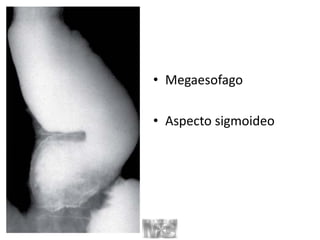

DIAGNOSTICO

1. Esofagograma con bario

• Imagen en:

– “pico de pajaro”

– “punta de lápiz”

• Dilatacion del cuerpo

esofagico

• Megaesofago

• Aspecto sigmoideo